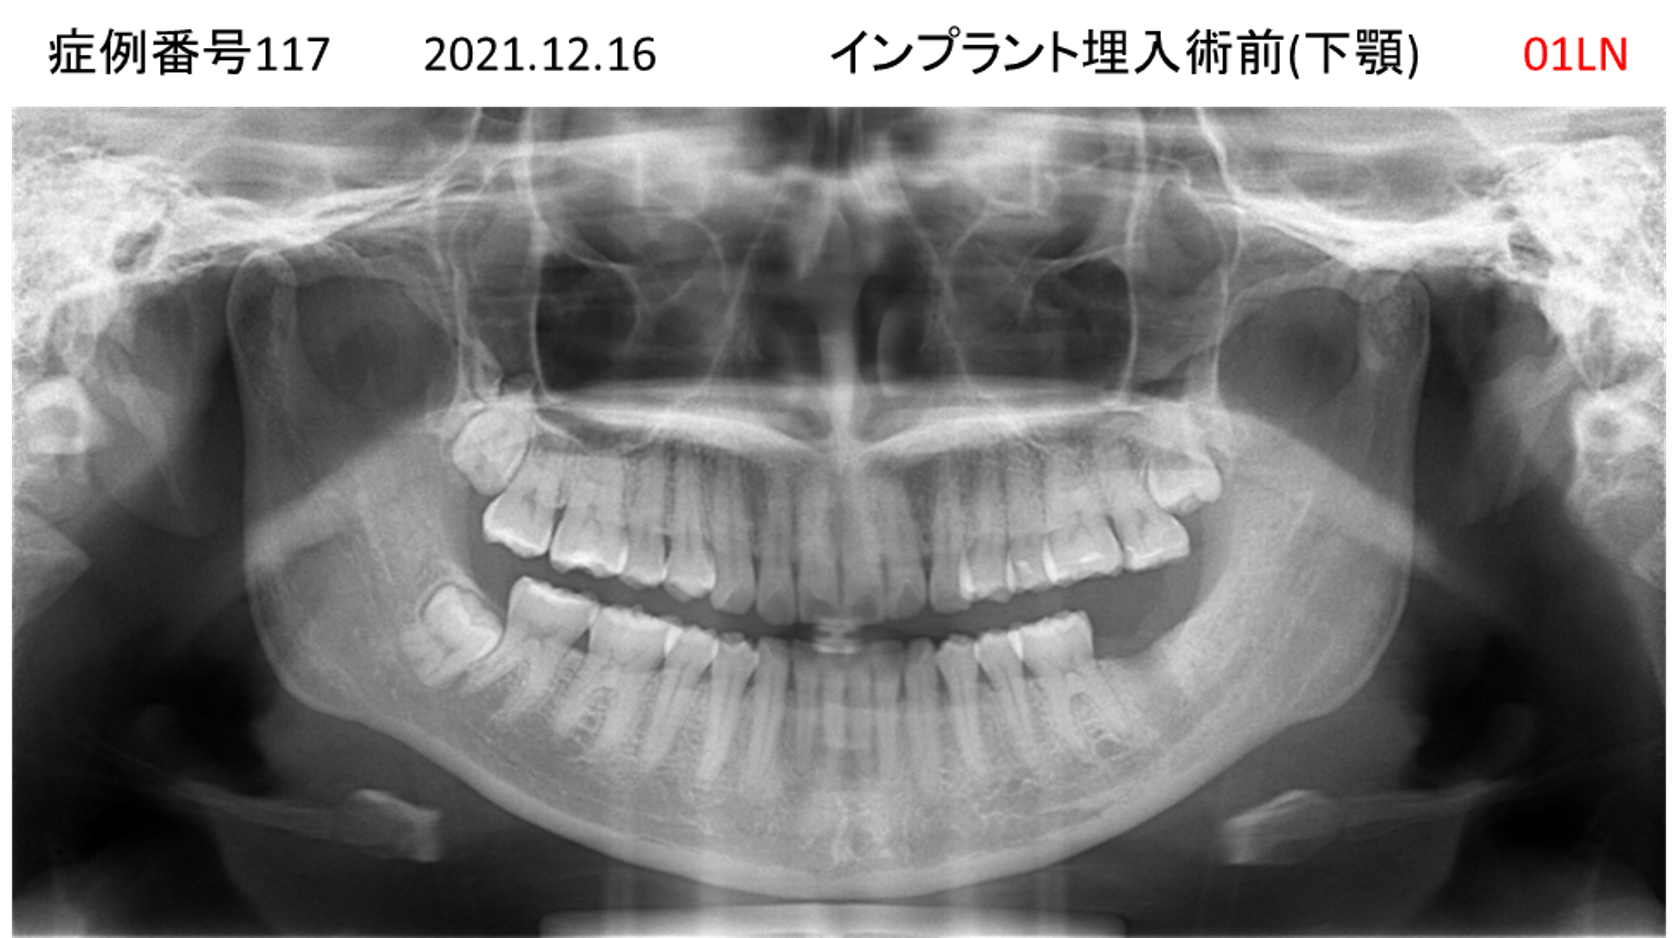

上の前歯が揺れてきてかめない患者様のインプラント症例

| 患者さんの症状(主訴) |

上の前歯が揺れてきた。かめない |

| 治療内容 |

サイナスリフト、GBR、インプラント、即時荷重 |

| 治療結果 |

上の前歯の揺れが収まった。奥歯でしっかり噛める。 |

| 治療の注意点(リスク/副作用) |

インプラントが壊れたら再治療が必要 |